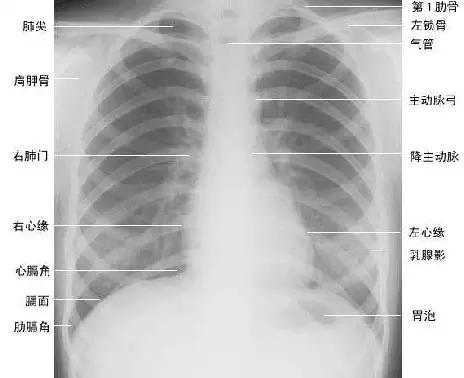

正常胸部后前位片

下面为大家依次介绍胸部正常X线解剖

2、肺纹理

肺纹理为自肺门向肺野呈放射状分布的树枝状阴影,它主要是肺动脉的投影,肺静脉、支气管和淋巴管也参与形成。肺纹理由肺门向外围延伸,逐渐变细,至肺野外带渐细小而稀少,距侧胸壁内缘约1cm范围内的肺野基本无肺纹理可见(图下图)。